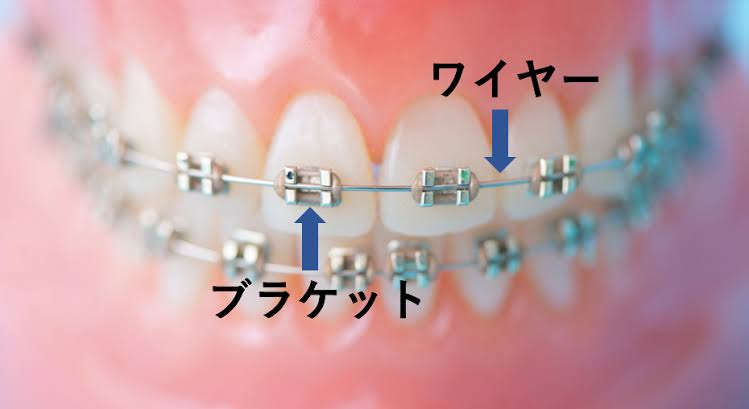

①ブラケットを使うやりかたは、(オールマイティーに使える便利な手法ではありますが)、

永久歯を2〜4本抜いてスペースを作り、ワイヤーを絞めて寄せていきます。その際に痛みは伴うし、ブラケットが付いている歯は歯磨きしにくいので虫歯のリスクは高まります